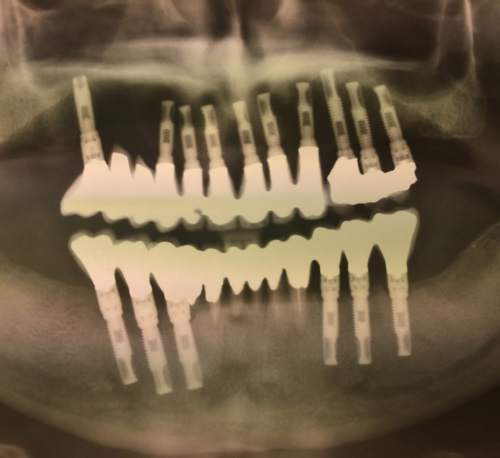

La "vite" è filettata all'esterno e all'interno: esternamente per avere un'ottima presa sul tessuto osseo del processo alveolare superiore o inferiore, internamente per consentire il posizionamento della protesi definitiva che è l'unica parte visibile e ricalca quella che è l'anatomia dell'elemento sostituito.

Questa tecnica rende possibile la sostituzione o di un singolo elemento ma può arrivare, attraverso l'uso di più impianti, a curare una totale edentulia dell'arcata superiore o inferiore.

Il Dottore vanta una casistica notevole sia per impianti a carico differito (l'elemento protesico viene montato almeno 8 settimane dopo l'inserimento dell'impianto) o a carico immediato (permette al Paziente di passare in meno di 36 ore dall'assenza di uno più elementi a una dentatura completa, esteticamente e funzionalmente valida).

Ogni intervento di implantologia viene preceduto da una diagnosi tramite Tc Cone Beam 3D di ultima generazione.